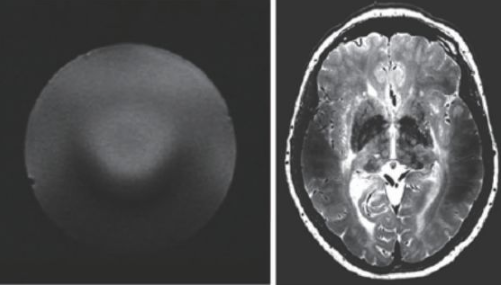

超(chao)高(gao)場MRI的(de)(de)(de)射(she)頻(pin)場設計(ji)也是一(yi)個較為困(kun)難(nan)的(de)(de)(de)問(wen)題(ti)。由于(yu)射(she)頻(pin)頻(pin)率超(chao)過了(le)300 MHz,介(jie)電常數(shu)引起的(de)(de)(de)問(wen)題(ti)非(fei)常突出。圖(tu)13 是一(yi)個在(zai)7 T 下的(de)(de)(de)成像(xiang)結果,可以(yi)看到(dao)在(zai)圖(tu)像(xiang)內部(bu)(bu)的(de)(de)(de)信號非(fei)常不均(jun)勻(yun),由于(yu)射(she)頻(pin)波(bo)長的(de)(de)(de)極度縮短,組織(zhi)的(de)(de)(de)介(jie)電常數(shu)對射(she)頻(pin)場的(de)(de)(de)分布有極大的(de)(de)(de)影響(xiang),這也是目(mu)前(qian)超(chao)高(gao)場MRI 需(xu)要(yao)解決(jue)的(de)(de)(de)重要(yao)問(wen)題(ti)之(zhi)一(yi)。目(mu)前(qian)的(de)(de)(de)9.4 T以(yi)上的(de)(de)(de)MRI設備還難(nan)以(yi)獲得人體體部(bu)(bu)掃描的(de)(de)(de)良好圖(tu)像(xiang),其(qi)主要(yao)應用還是做(zuo)頭部(bu)(bu)的(de)(de)(de)掃描。

圖13 超高(gao)場下的射頻場不均勻性